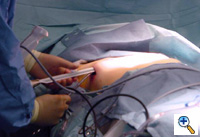

Once the tunnel reaches the sternum, the endoscopic tunneling device is utilized to visualize the clamp entering the interspace of maximal pectus depth and passing retrosternal (Figure 7). At the level of the sternum, these tunnels go retrosternal and communicate with each other. Ideally, even after entering the interspace, the tunnel stays extrapleural. The endoscopic view of the tunnel allows visualization of the safe passage of the clamp under the sternum and anterior to the pericardium. The mediastinum and pericardium can be seen pulsating posterior to the clamp. Two monitoring screens are utilized in order to allow excellent visualization by both the surgeon and assistant (Figure 8). Eventually, the larger curved clamp is easily passed under the sternum (Figure 9). This clamp is thus passed through one midaxillary skin incision and out the other midaxillary skin incision.

The clamp is then opened and used to grasp an umbilical tape and pull the tape through the tunnel (Figure 10). This umbilical tape is tied to two more umbilical tapes so that one tape can be used to pull a flat mediastinal tube through the tunnel and the second umbilical tape can act as a back-up. One umbilical tape is tied to a flat mediastinal tube. Then, this flat mediastinal tube is lubricated (Figure 11) and pulled through the tunnel and used to gently dilate the tunnel. The tunnel pathway is then endoscopically inspected to confirm hemostasis and satisfactory position of the flat mediastinal tube (Figure 12 ).